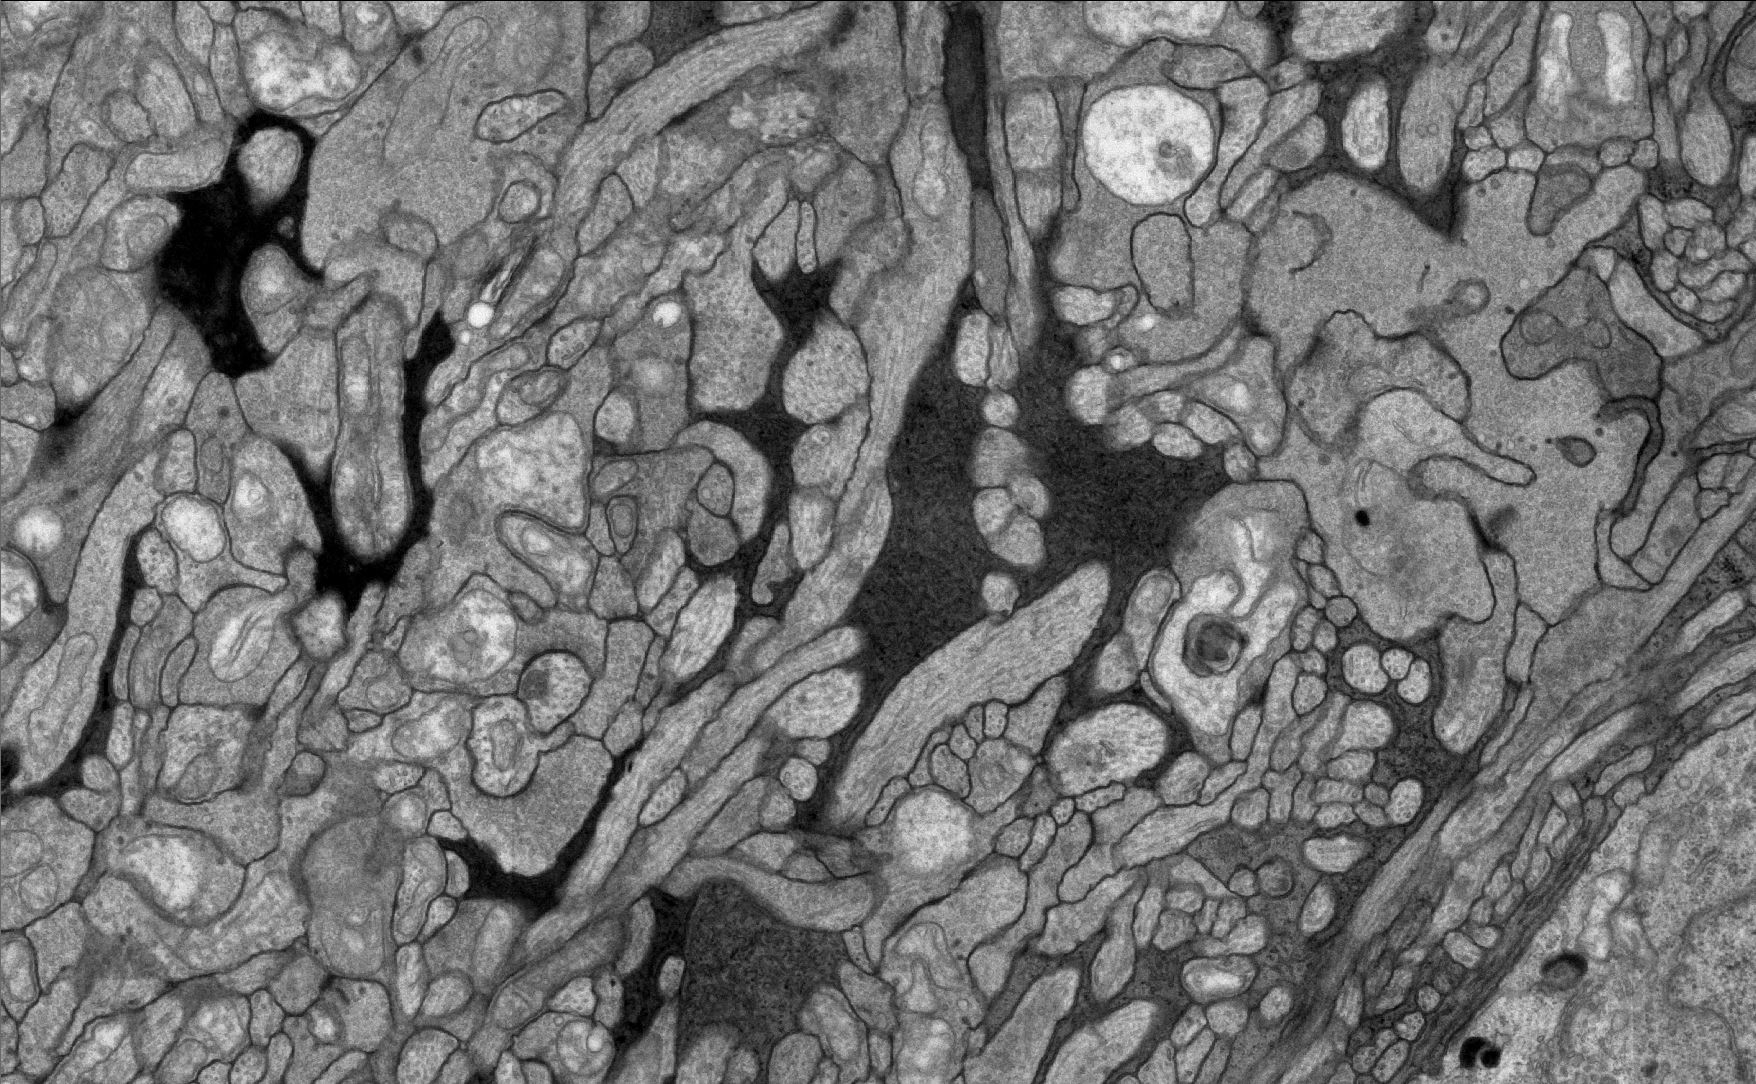

What you are seeing above is a view of the ultrastructure of the inner plexifom layer of the retina with connections between bipolar cells, amacrine cells, ganglion cells with Müller cells in-between them all.

Continuing on the theme of disease in the retina, I’ve been looking at lots of early alterations in the structure and circuitry of diseased retina. Its both beautiful and horrifying. Beautiful in the sense that the biology in the normal retina is so precise and elegant. Horrifying in the sense that it is such a complex system that we are elucidating by connectomics approaches and there are so many opportunities for circuitry to become corrupted. Finding precise places and timing of alterations in the circuitry of retina is a huge challenge.